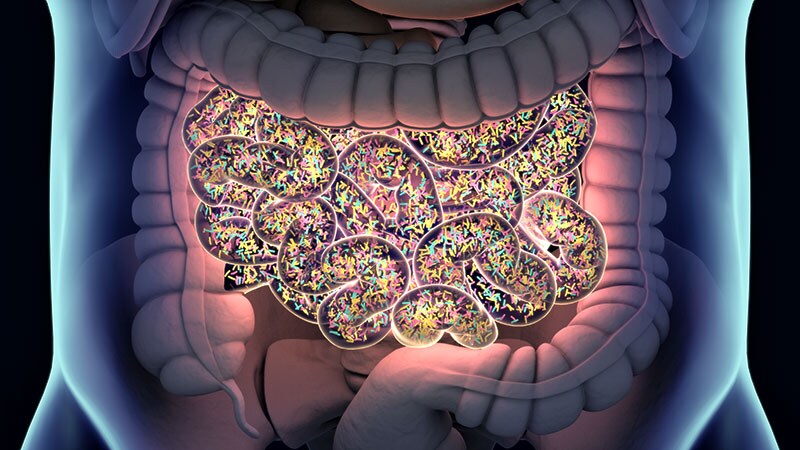

• CHEST 2023 Dietary Changes to Microbiome May Improve Lung Function A study of firefighters who worked at the World Trade Center in New York in the aftermath of the 9/11 attacks suggests that a low-cal Mediterranean diet may protect against lung dysfunction.